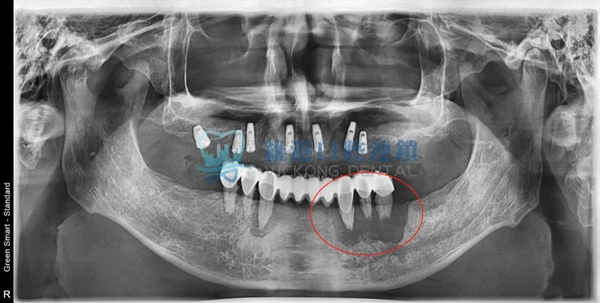

根尖囊腫案例展示

嚴重案例

頜面囊腫波及根尖